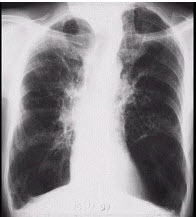

193、单项选择题

女,28岁,反复咯血半月余,CT检查如图,选出最可能的诊断()

A.肺结核

B.肺癌

C.间质性肺炎

D.支气管扩张

E.肺脓肿

194、单项选择题 男性18岁,阵发性晨间咳嗽3周,偶胸闷、憋气,查体双肺偶闻哮鸣音,追问病史患者2个月前有上呼吸道感染史,闻刺激性气味引起咳嗽,为明确诊断,下列哪项检查最有价值()